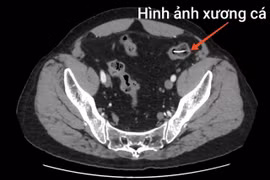

Bệnh viện Bệnh Nhiệt đới Trung ương vừa phẫu thuật cấp cứu thành công cho một người đàn ông bị dị vật xương cá đâm thủng ruột non, gây viêm ổ bụng.